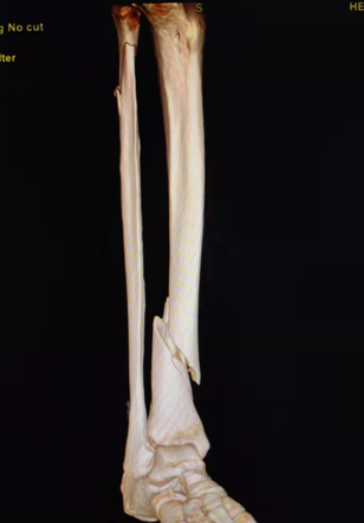

典型病例:女性,56歲,術(shù)前CT提示脛骨中下段骨折,移位明顯。

術(shù)后正側(cè)位片提示骨折達解剖復(fù)位,力線恢復(fù)正常。